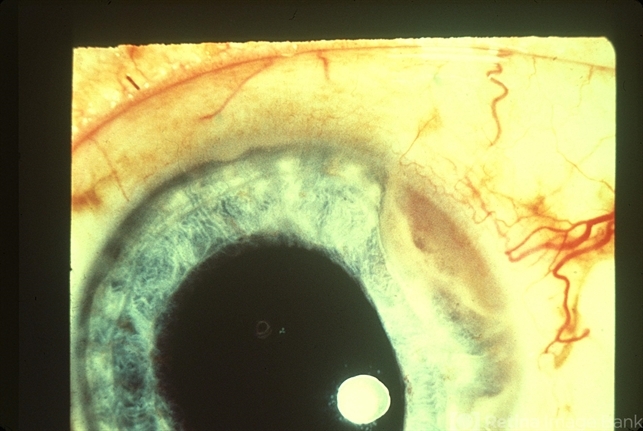

Ciliary Body Tumor

ciliary body tumor, feeder vessel

Body tumor with dilated feeder vessel.